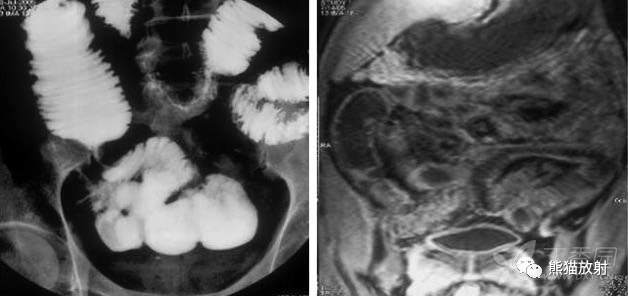

回盲部结核

ILEOCAECAL TUBERCULOSIS

Fleischner征:回盲瓣增厚伴回肠末端狭窄;CT示回肠末端狭窄伴瓣膜区增厚。

回盲部的早期受累是明显的痉挛和运动亢进伴瓣膜水肿。回盲瓣唇增厚和/或张开瓣膜,末端回肠 ( Fleischner或“倒置伞”征) 被认为是结核的特点。

回盲部肠腔持续性狭窄

盲肠短缩伴末端回肠悬吊

回盲部环形缩窄

CT显示回肠末端和盲肠壁增厚伴肠石,周围间隙混浊

肠灌肠 (A) MRI肠灌肠 (B) 显示回肠局部狭窄,近侧肠腔扩张,局部肠壁增厚(>3mm为异常),明显强化。

盲肠壁增厚伴周围炎性改变